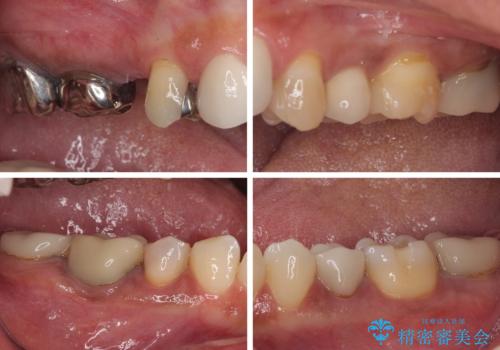

- 20年ほど前に被せた前歯のメタルボンドクラウンの色合いを気にして来院された患者様です。

2歯をオールセラミッククラウン(ジルコニアクラウン)にて補綴することとしました。

裏打ちが金属の場合、どうしても金属色を遮蔽しないとならないため、透明感のない色合いとなってしまいます。

土台の金属はグラスファイバーを含有したものに、クラウンの土台は強化セラミックとすることで、自然な前歯に仕上がりました。